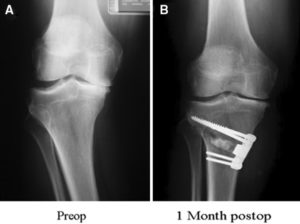

Osteotomy. In a knee osteotomy, either the tibia (shinbone) or femur (thighbone) is cut and then reshaped to relieve pressure on the knee joint. Knee osteotomy is used when you have early-stage osteoarthritis that has damaged just one side of the knee joint. By shifting your weight off the damaged side of the joint, an osteotomy can relieve pain and significantly improve function in your arthritic knee

Your doctor may recommend surgery if your pain from arthritis causes disability and is not relieved with nonsurgical treatment. You doctor will discuss the most appropriate surgery for you.